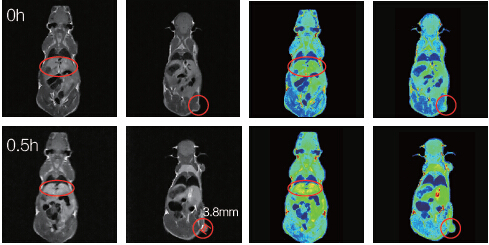

利用1T-MRI可以實(shí)現(xiàn)小鼠生理特征的定量計(jì)算,包括組織體積、腫瘤的尺寸、造影效果定量化評(píng)價(jià)等;MRI方法無(wú)需處死老鼠,簡(jiǎn)單快速,提高了實(shí)驗(yàn)結(jié)果的可靠性、實(shí)驗(yàn)速度與實(shí)驗(yàn)的連續(xù)性。

小鼠腫瘤直徑3.8mm;打入新型Mn螯合造影劑0.5h之后,通過(guò)灰度平均值計(jì)算,發(fā)現(xiàn)肝臟與腫瘤造影明顯。